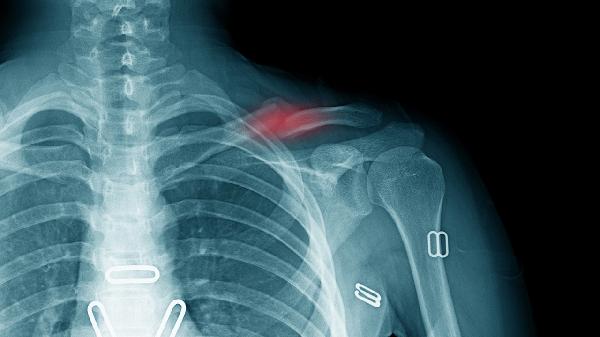

开放性骨折清创不彻底或内固定物污染可能引发慢性骨髓炎。炎性介质会溶解新生骨组织,伴随窦道渗出和低热症状。需取分泌物培养后使用注射用头孢呋辛钠抗感染,严重者需取出内固定并植入抗生素骨水泥间隔器。

糖尿病血糖控制不佳或甲状旁腺功能亢进会干扰钙磷代谢。骨质疏松使骨折端吸收大于成骨,表现为骨痂稀少且骨折线清晰。需口服阿仑膦酸钠片改善骨密度,同时治疗原发病,监测血清钙磷水平。